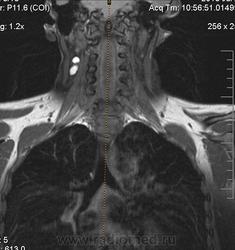

Сирингомиелия шейно-грудной локализации? Аномалия Арнольда-Киари I. Платибазия.

здоровенная сирингогидромиелитическая киста (по видимому, "высокого давления"), мальформация Киари 1.   также имеются признаки внутренней окклюзионной гидроцефалии.

Cпасибо большое, как вы думаете, это  кисты в области мягких тканей шеи справа (гиперинтеснивные по Т1 и Т2), или что-то другое?

морфологически- явно кистозные образования. А вот их происхождение - вопрос.